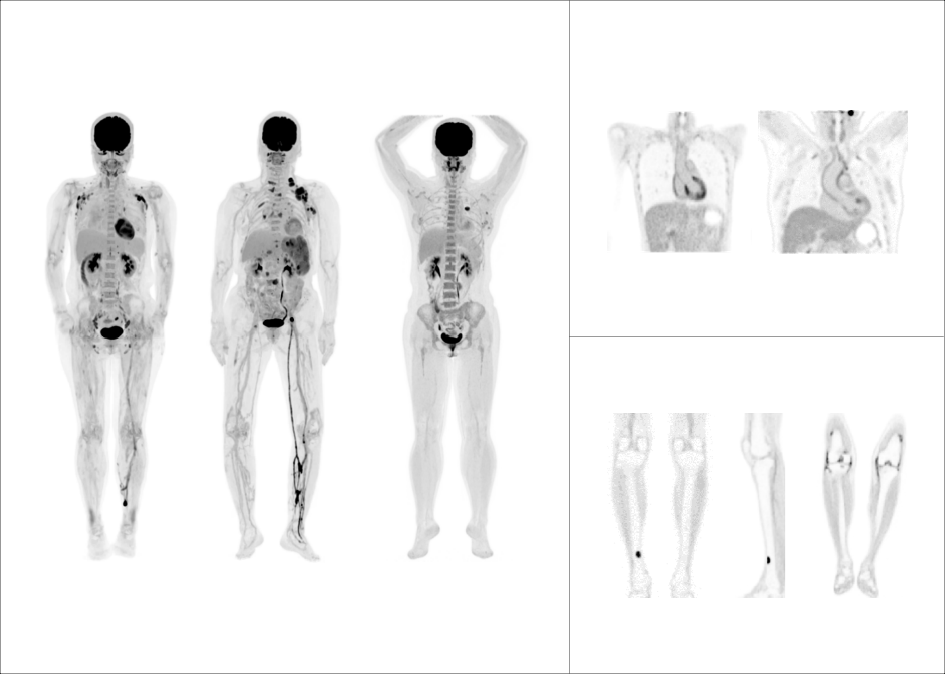

微小淋巴结高清显像

大体重患者主动脉血管结构清晰显示